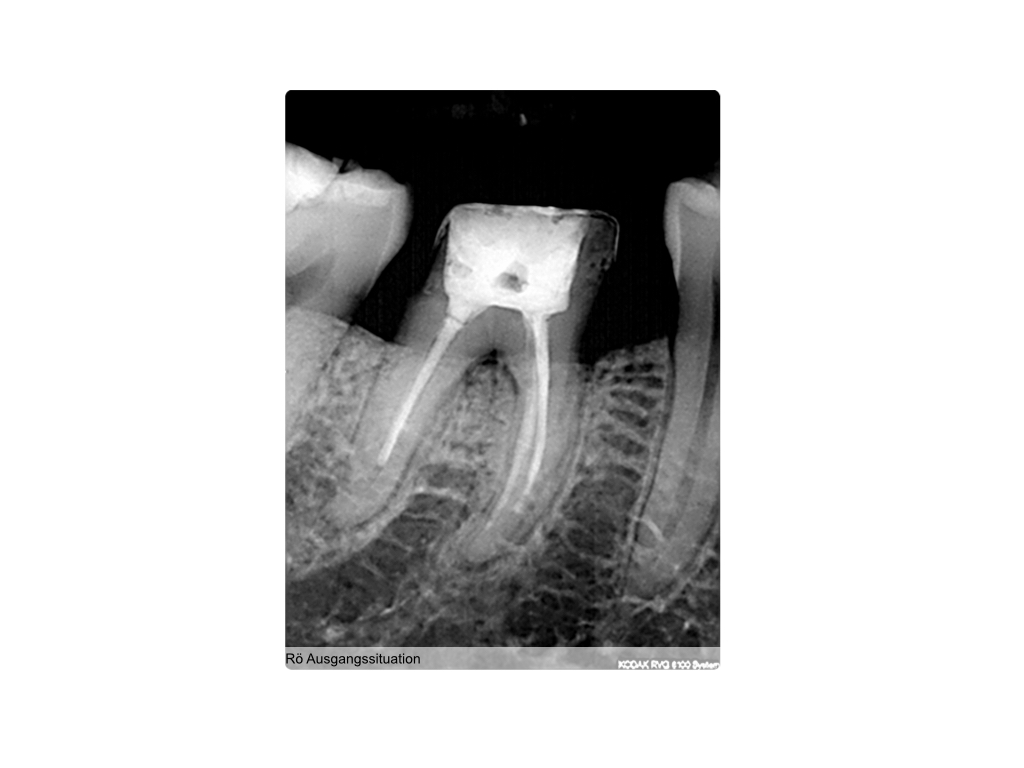

Saving hopeless teeth (36)